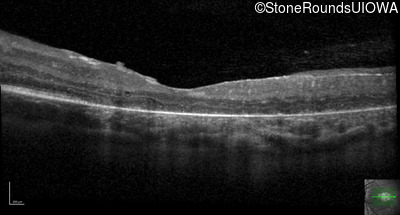

Optical Coherence Tomography - Left - 20/80 -1

Exemplar / OCT Stack